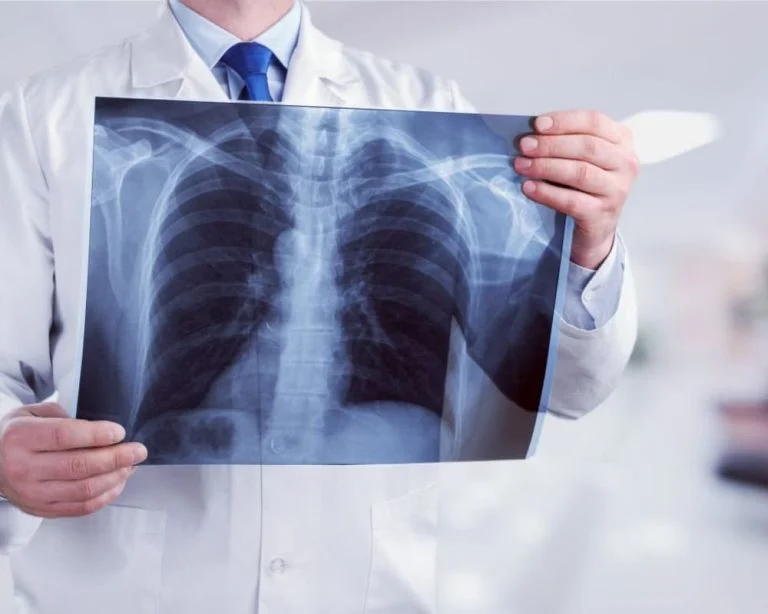

З 30 по 4 січня до Дар’ївської та Білозерської громад Херсонщини заплановано виїзди мобільного кабінету рентгенодіагностики.

Під час флюрообстеження можна отримати консультацію лікаря-фтизіатра та на місці пройти швидке тестування на інфекційні захворювання, йдеться в дописі.

За даними департаменту здоров’я Херсонської ОДА, впродовж листопада-грудня 2023 року було проведено флюорографічне обстеження 2614 осіб із 17 населених пунктів Білозерської, Дар’ївської, Чорнобаївської та Музиківської громад.

Скринінгове флюорографічне обстеження дає можливість на ранніх стадіях діагностувати як туберкульоз, так й інші захворювання органів грудної клітки.